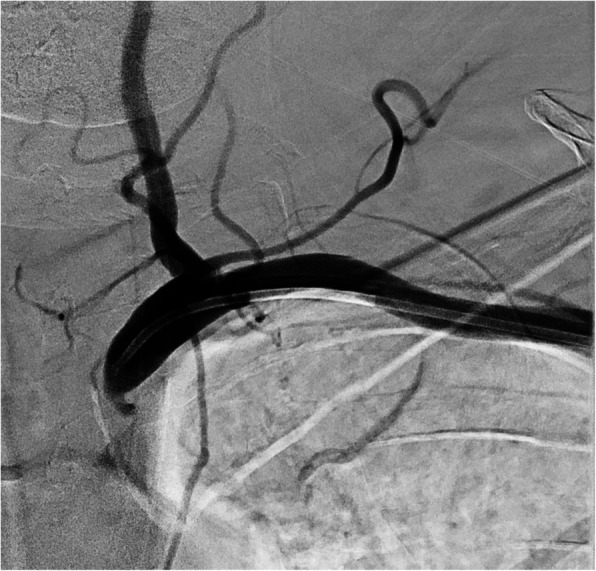

Fig. 3.

Digital subtraction angiogram (DSA) of a high-grade subclavian stenosis, treated with retrograde brachial access